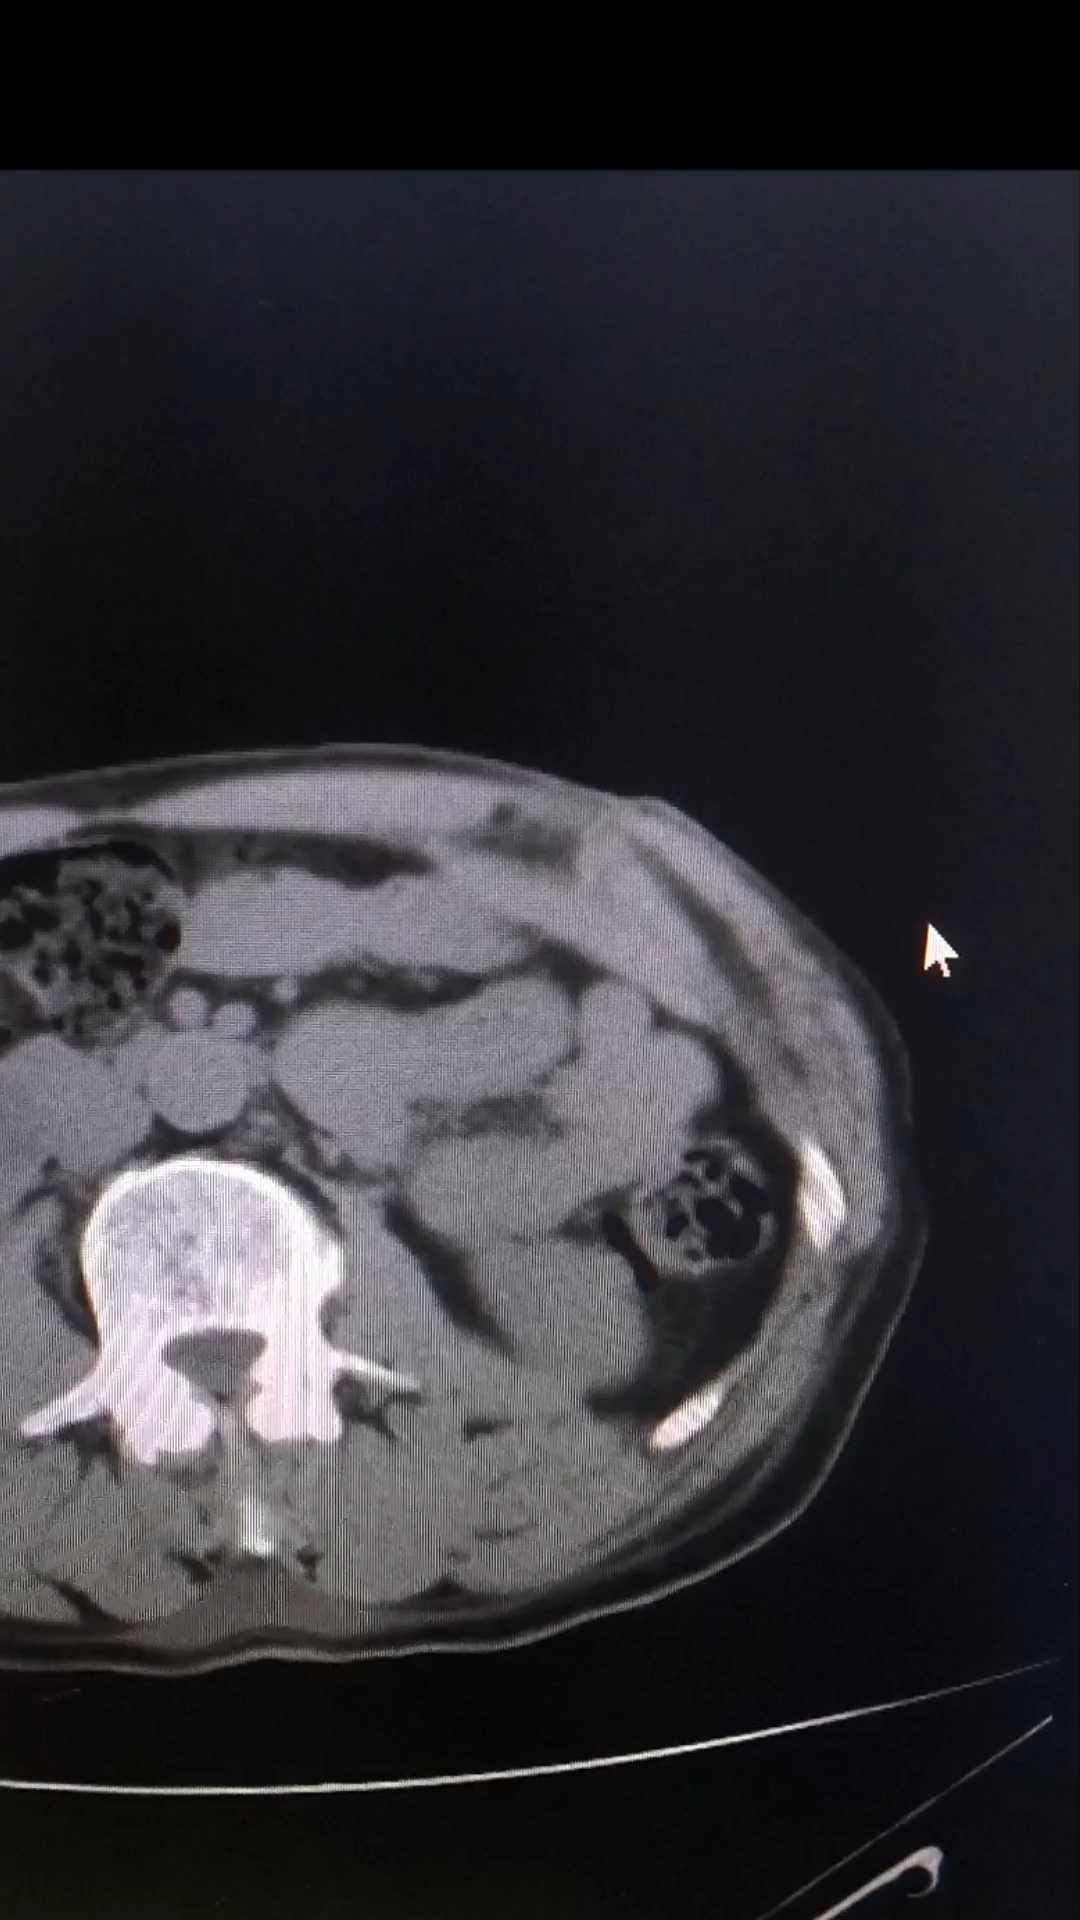

【治疗经过及结果】:急诊下完善腹部CT检查,未发现膈下游离气体,给予局麻下扩创探查,未探及腹膜损伤,随缝合治疗,术后3日常规复查,发现腹腔气体,无创面以外腹痛。